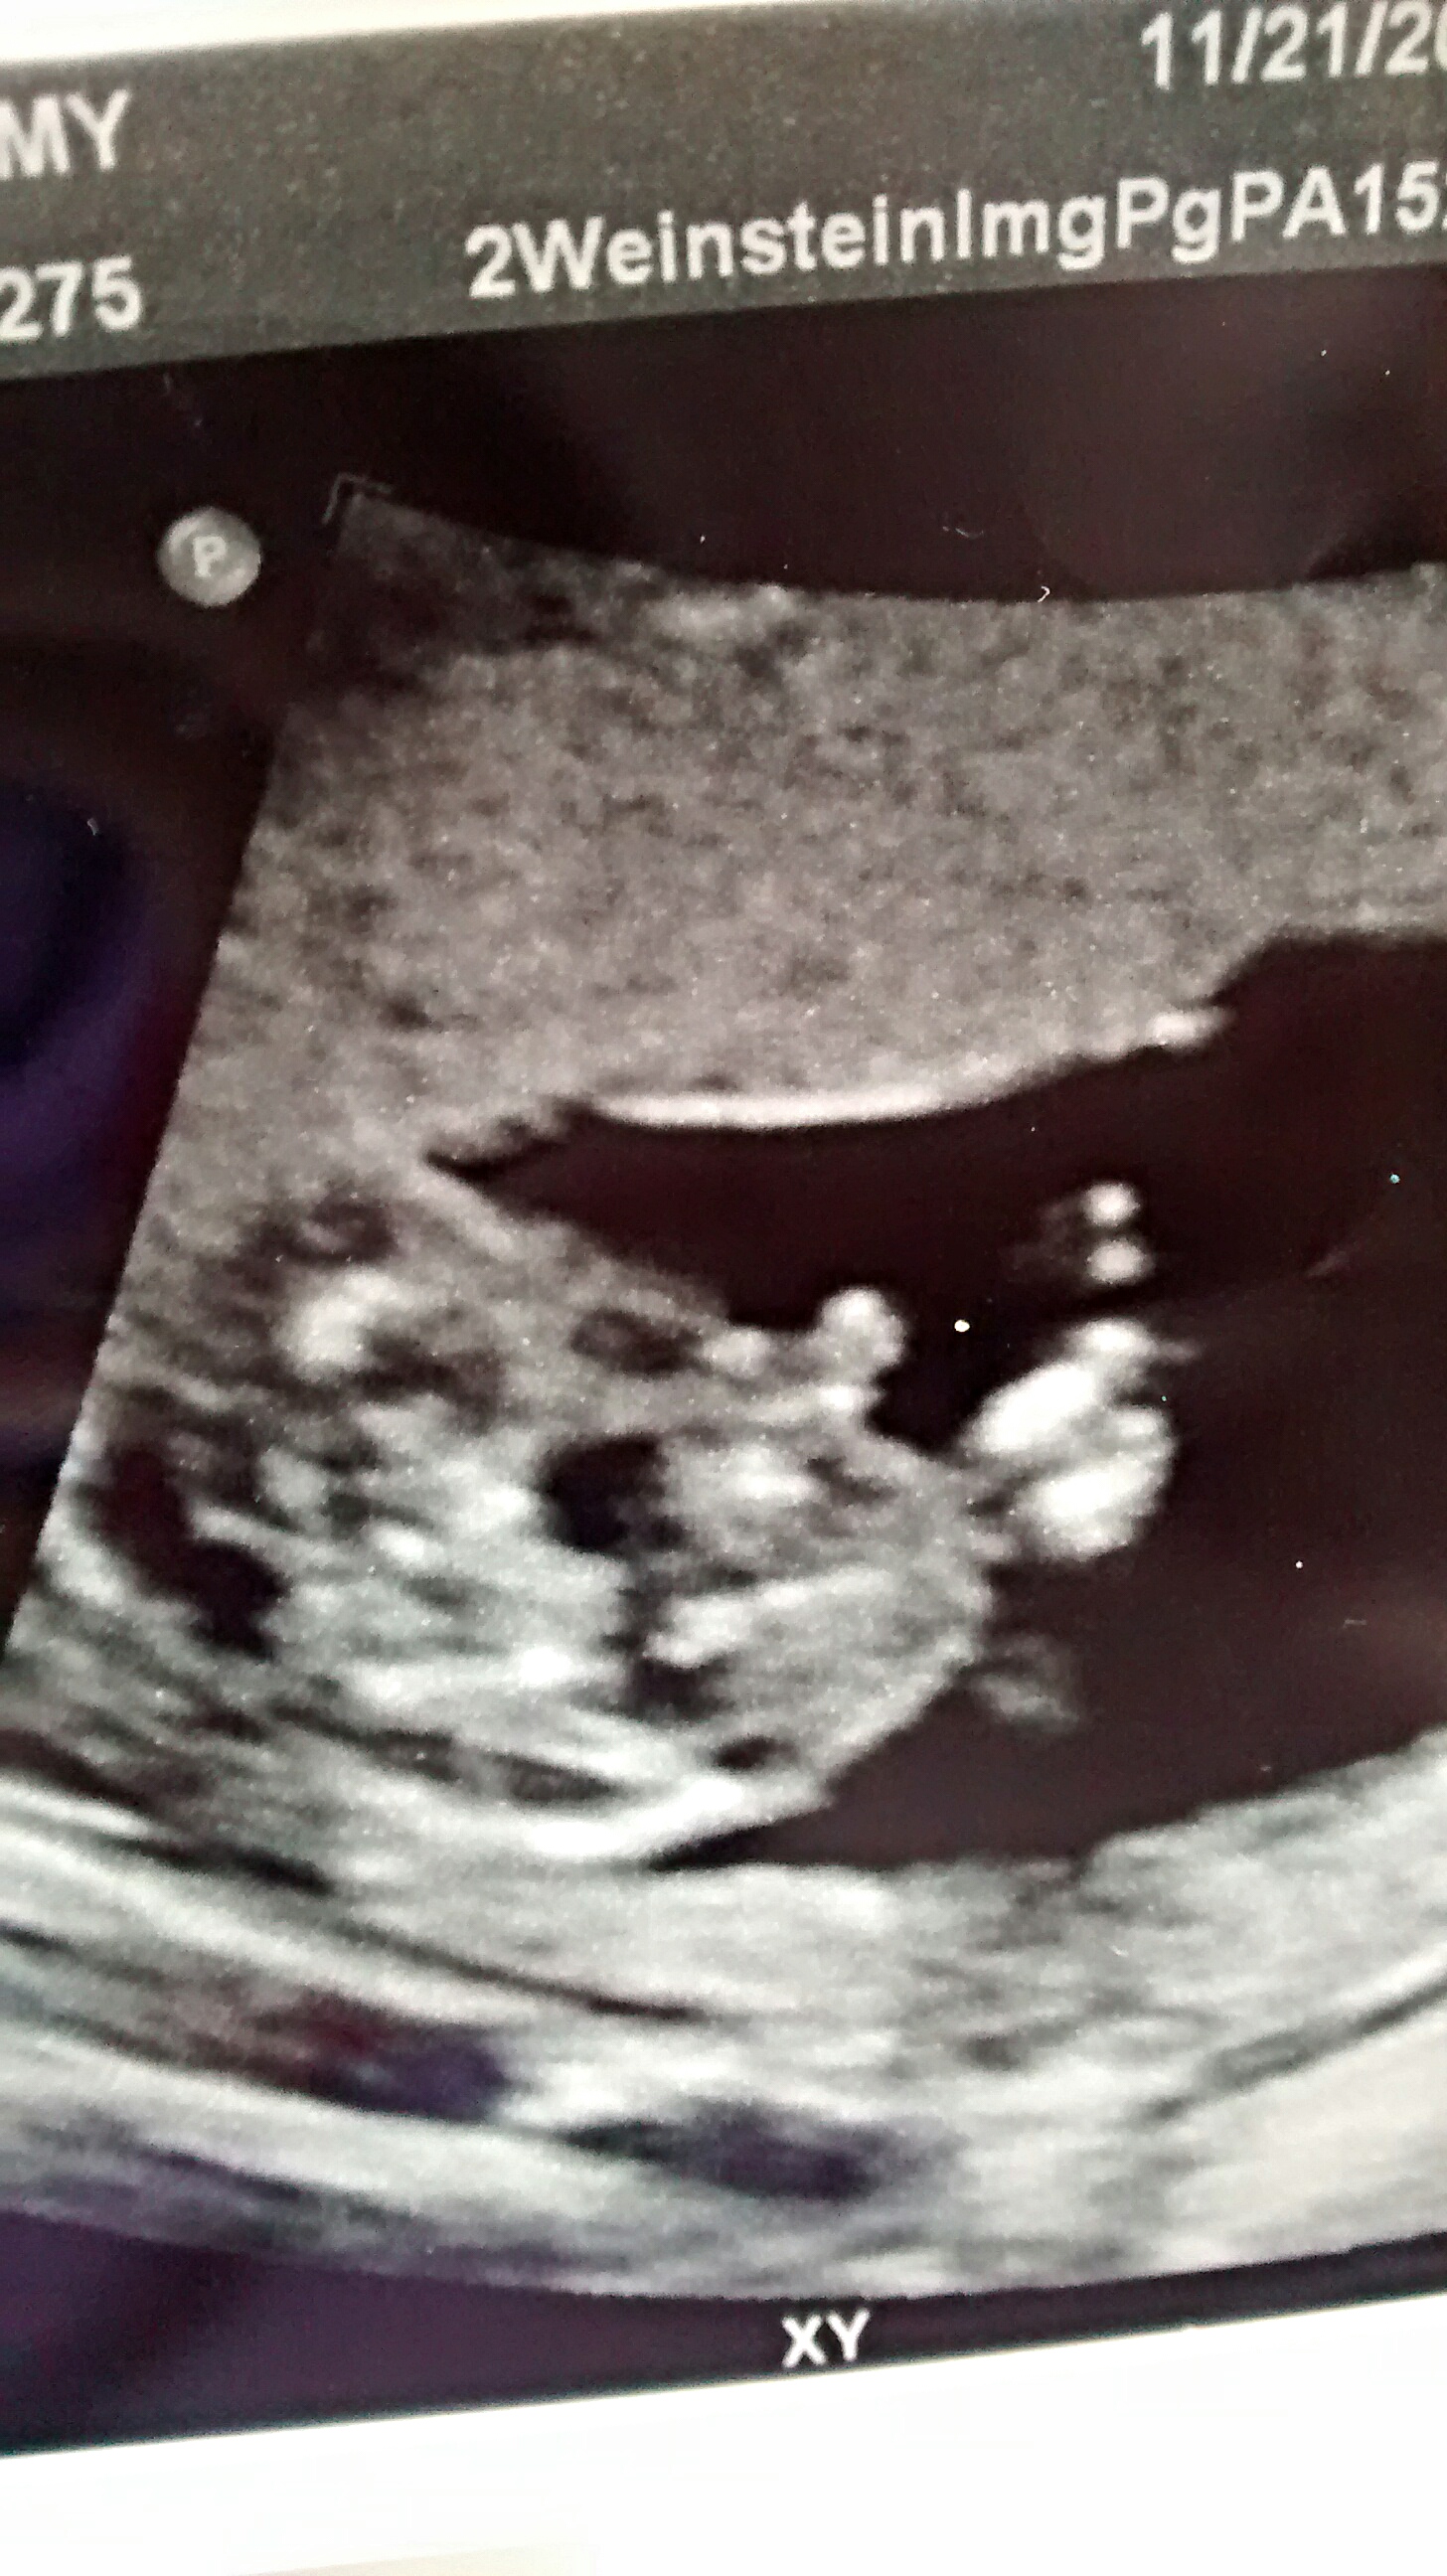

Do you have a potty shot at all? Thinking maybe boy but won't say for sure x

No potty shot. I was told probably boy by the tech. But it didn't sound 100%.

Look like a boy to me.